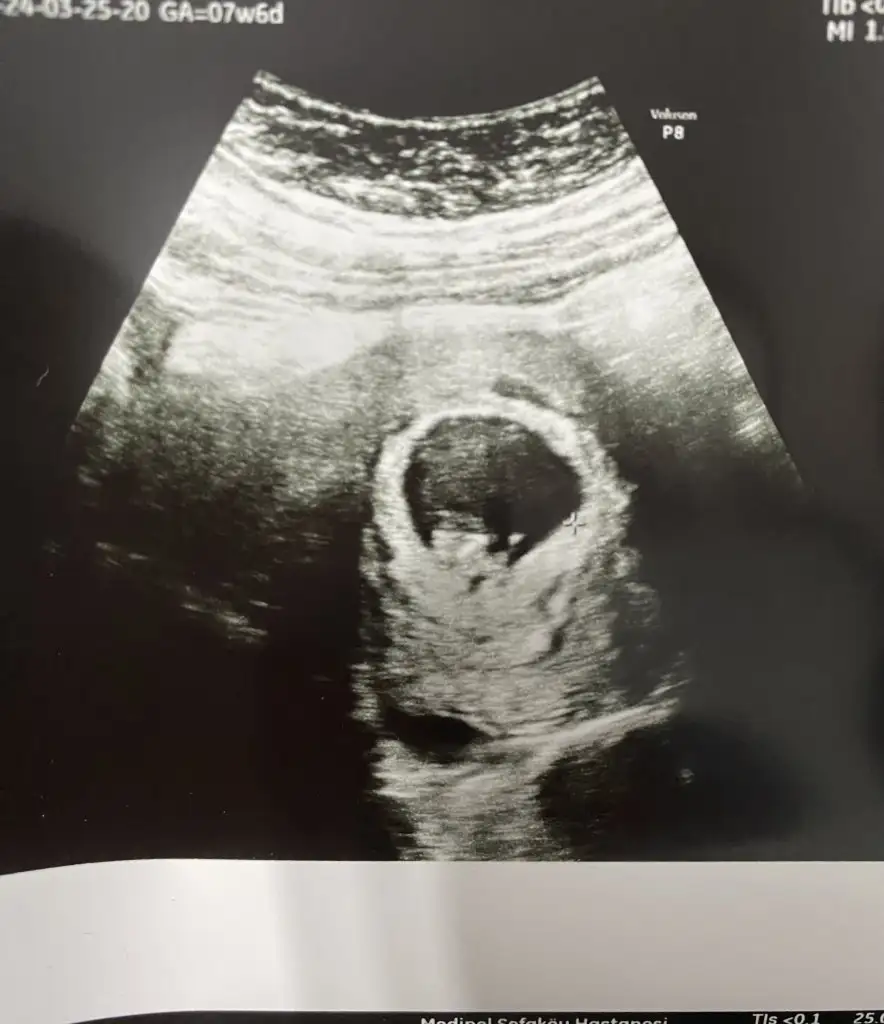

Merhaba lütfen bana da bakabilir misiniz 7 hafta 6 günlük karından usg

Eklentiler

• IMG_1056.webp

31,2 KB · Görüntüleme: 105

• IMG_1055.webp

37 KB · Görüntüleme: 75